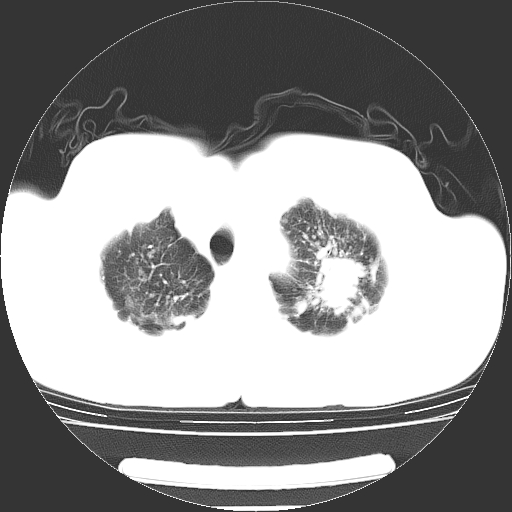

以下是引用yangyudong333在2008-4-29 5:38:00的发言:[br]比较典型的矽肺结节.支持[br]诊断依据:[br] 1.x线表现:[br] ①典型矽肺为多发直径 1~3mm 小结节,即矽结节,由胶原纤维和硅尘构成,可融合成团块,好发于上肺。[br] ②团块周围常有肺大泡。[br] ③胸内淋巴结增大、钙化。如肺门淋巴结呈蛋壳样钙化有助于与其他尘肺区别。[br] ④胸膜常广泛粘连、增厚。[br] 2.ct表现[br] ①两肺散在大小较为一致的小结节影,其密度较高,边界清楚。[br] ②小结节可融合为较大团块影,直径约 1cm ,甚至可达 10cm以上,易发生在上叶。[br] ③小结节周围常并有小叶中心气肿或弥漫性肺气肿。

以下是引用liuyue在2008-4-28 22:30:00的发言:[br]比较典型的矽肺结节.[br]请结合临床及化验除外矽肺合并肺结核之可能.